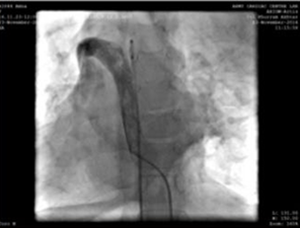

Veia femoral direita e artéria foram canuladas utilizando bainha radial 5F. Durante o procedimento, encontramos a veia cava inferior (VCI) drenando através da continuação azigosa para a veia cava superior direita e, em seguida, rastreando através do seio coronário dilatado no átrio direito. Foi tomada a decisão de realizar o procedimento a partir da veia jugular interna esquerda (acessada com bainha radial 5F).

Punção da veia jugular esquerda e cateter de angiografia 5F, mostrando veia superior do braço-veia cava superior-trajeto de conexão do átrio direito.